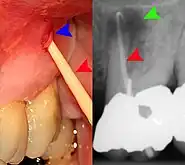

Decay (green) with apical abscess (blue)

Gutta-percha point indicating abscess origin